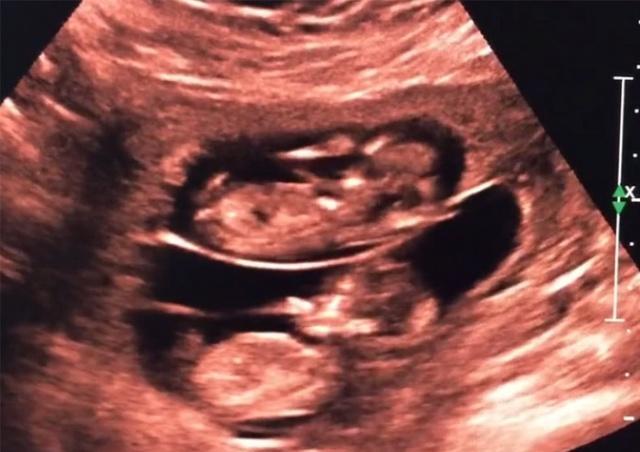

三个月双胞胎彩超图,三个月龙凤胎b超图

12周的双胞胎

孕妇去做彩超,看到双胞胎是这样的"姿势",网友直呼:神奇!